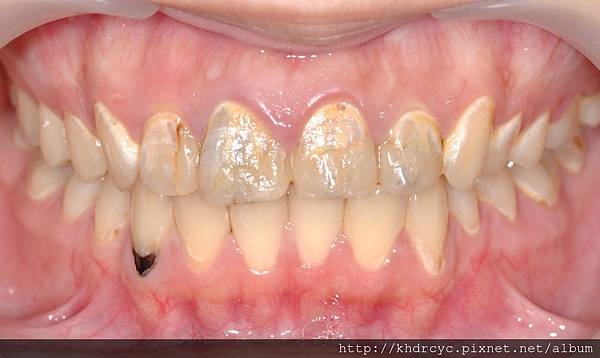

欣美牙醫首先幫仁武的C小姐

完成門牙治療包括根管治療與牙周病

改善牙齒結構與牙肉健康

過去因為對牙科的恐懼

已經忍受門牙爛掉的問題很久